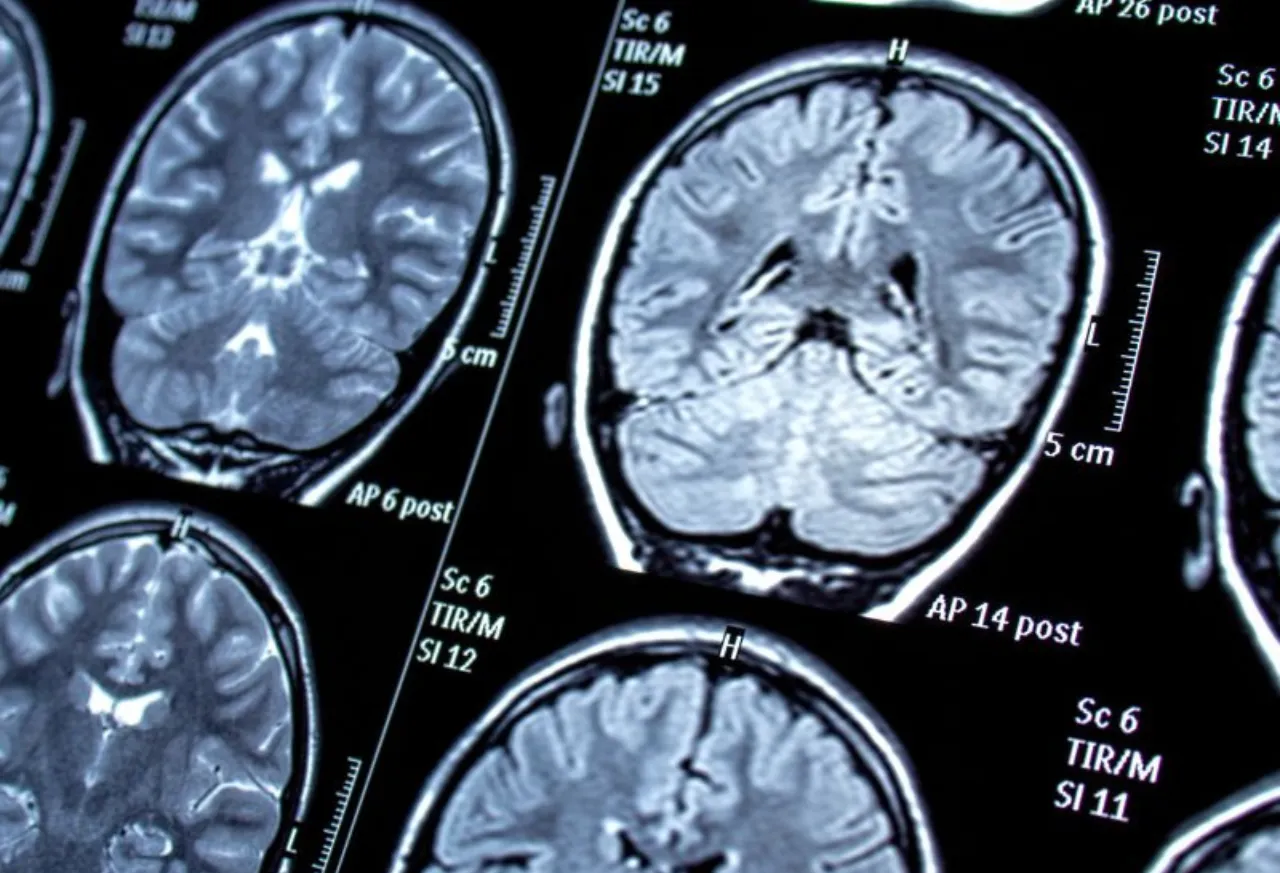

The brain is a complex organ composed of billions of neurons that communicate with each other through electrical impulses. Seizures occur when there is a sudden surge of abnormal electrical activity in the brain. This abnormal activity can be triggered by various factors, leading to different types of seizures. The origins of seizures can be broadly classified into several categories:

Abnormalities in the structure of the brain, whether congenital or acquired, can lead to seizures. Congenital abnormalities include conditions like cortical dysplasia, where the brain’s outer layer does not develop properly. Acquired structural abnormalities can result from traumatic brain injury, stroke, or tumours, all of which can disrupt normal brain function and trigger seizures.